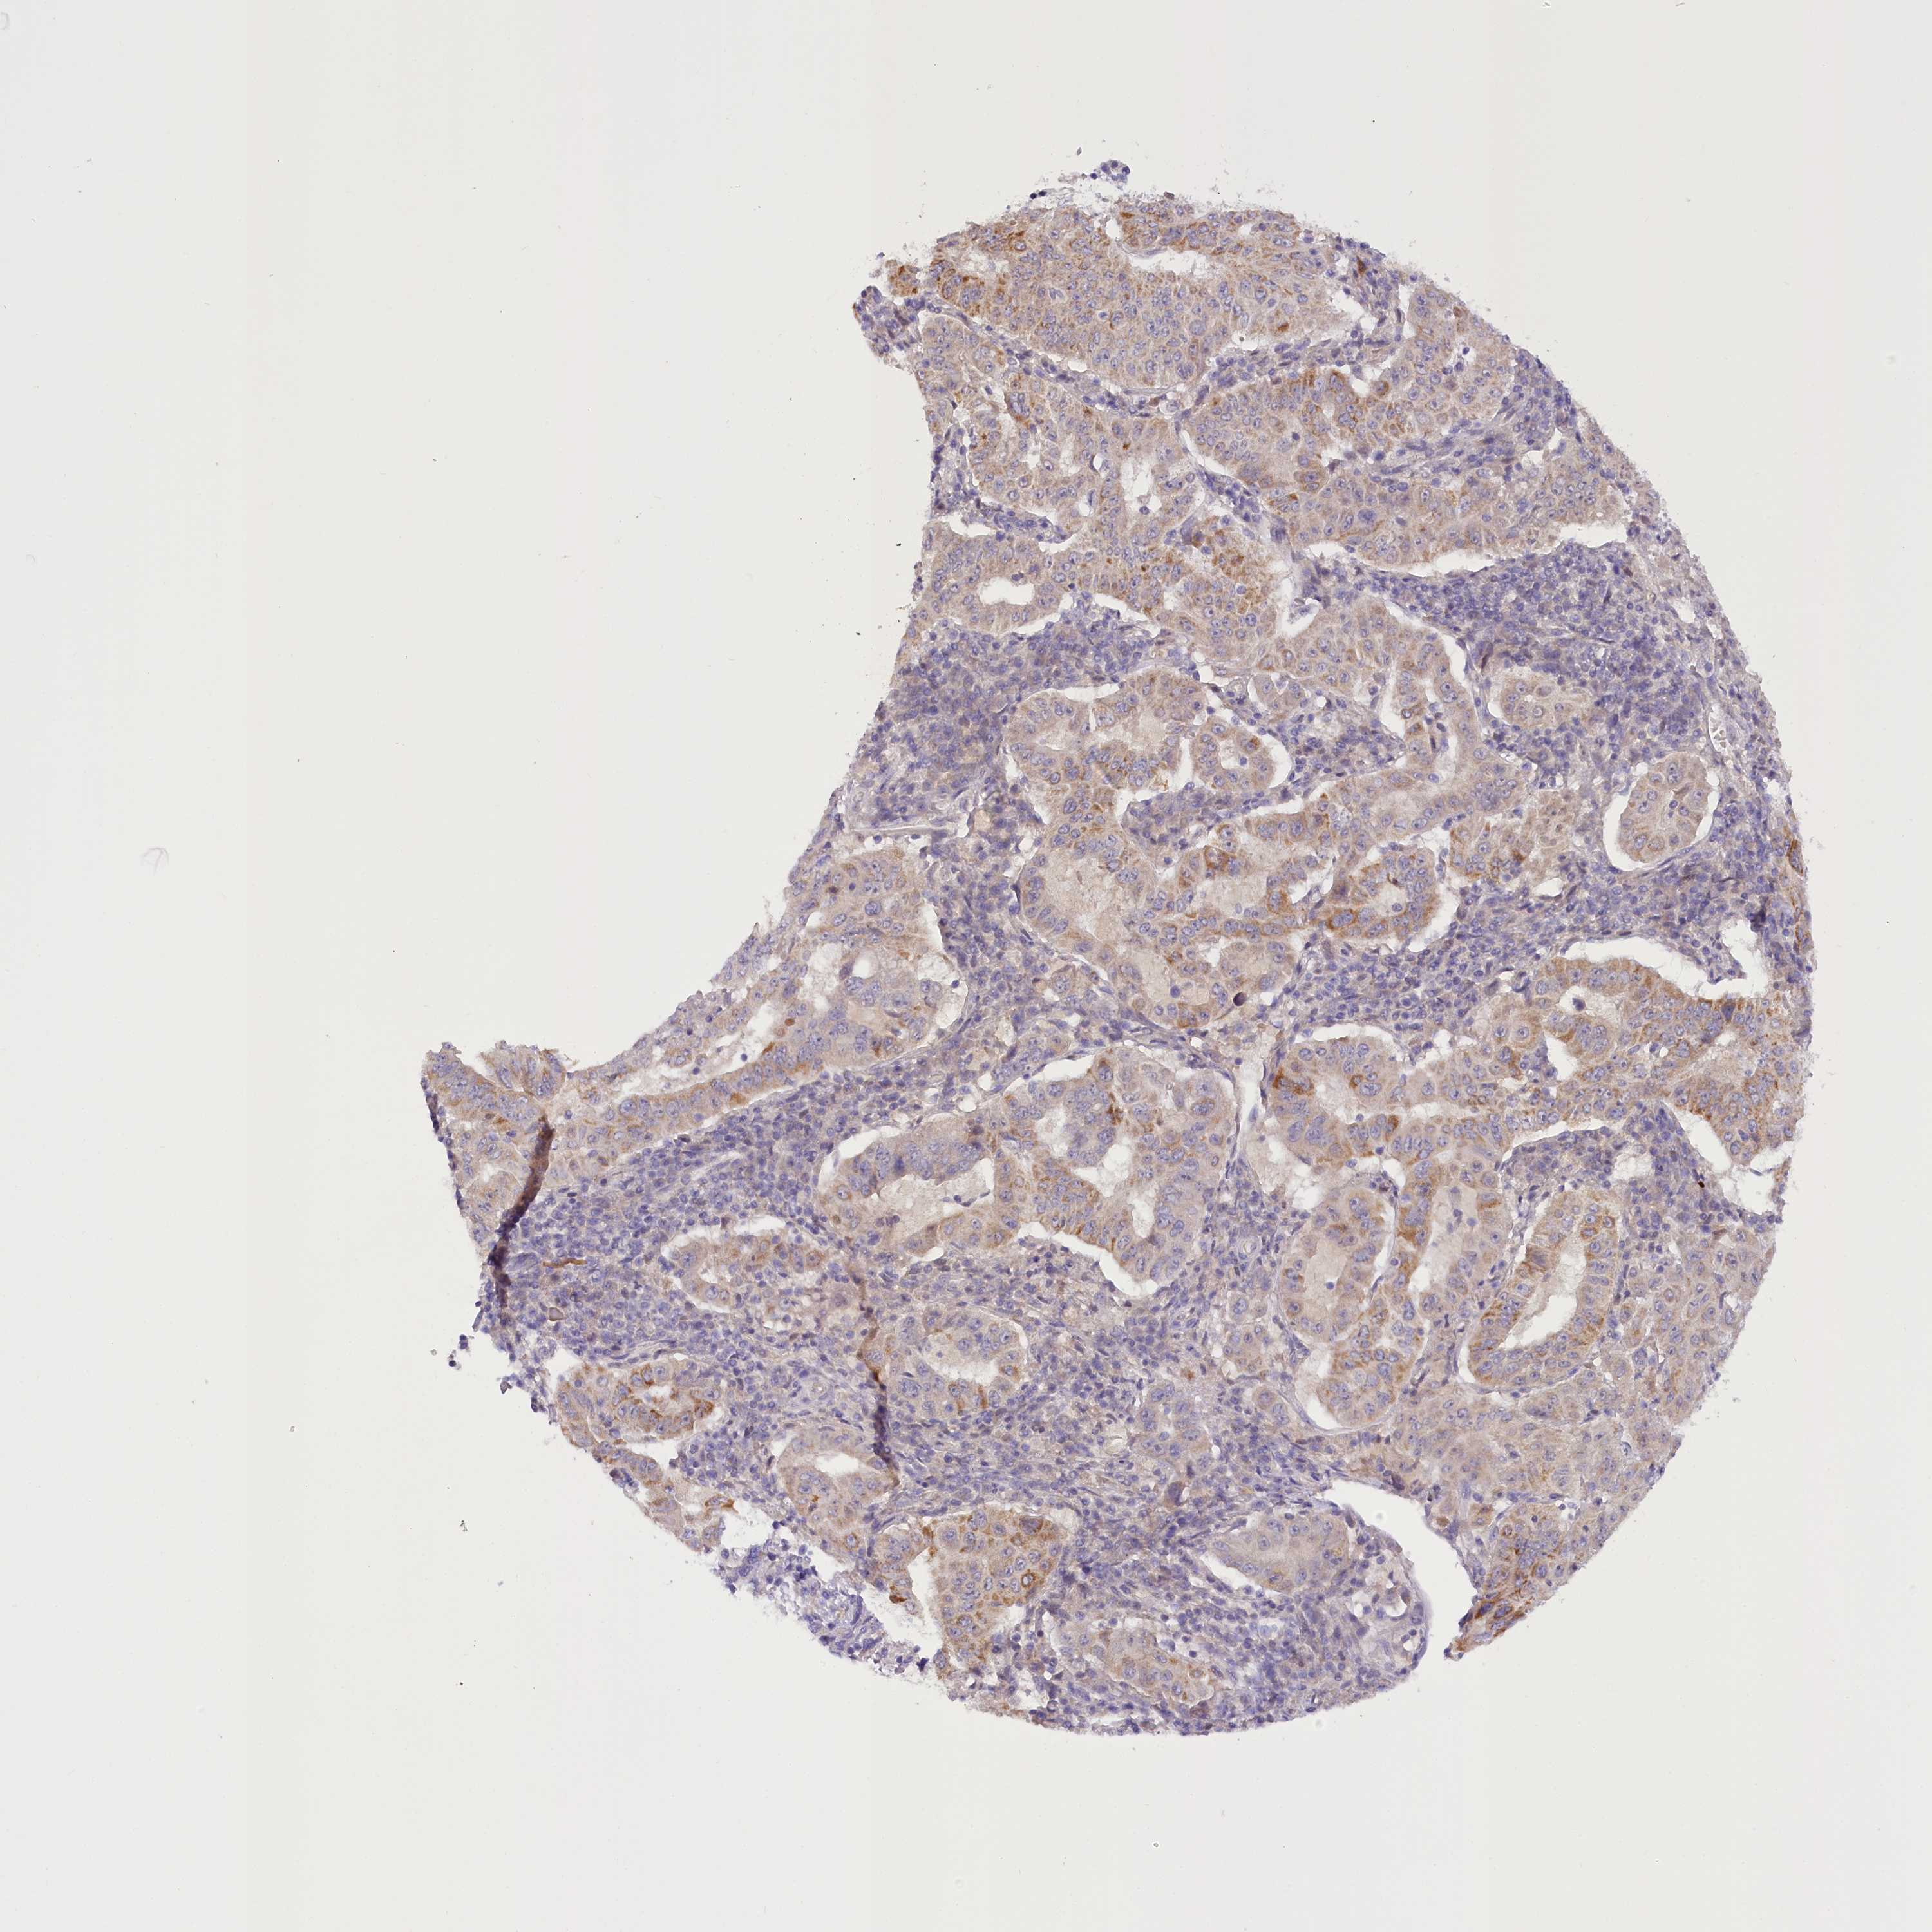

PANCREATIC CANCER - Protein expressioni

A mouse-over function shows sample information and annotation data. Click on an image to view it in a full screen mode. Samples can be filtered based on level of antibody staining by selecting one or several of the following categories: high, medium, low and not detected. The assay and annotation is described here.

Note that samples used for immunohistochemistry by the Human Protein Atlas do not correspond to samples in the TCGA dataset.

Antibody stainingi

Antibody staining in the annotated cell types in the current human tissue is reported as not detected, low, medium, or high, based on conventional immunohistochemistry profiling in selected tissues. This score is based on the combination of the staining intensity and fraction of stained cells.

Each image is clickable and will lead to virtual microscopy that enables deeper exploration of all samples and also displays staining intensity scores, fraction scores and subcellular localization as well as patient and tissue information for each sample.

Antibody HPA035911

Staining

High

Medium

Low

Not detected

Intensity

Strong

Moderate

Weak

Negative

Quantity

>75%

75%-25%

<25%

None

Location

Nuclear

Cytoplasmic/membranous

Cytoplasmic/membranous,nuclear

Adenocarcinoma, NOS